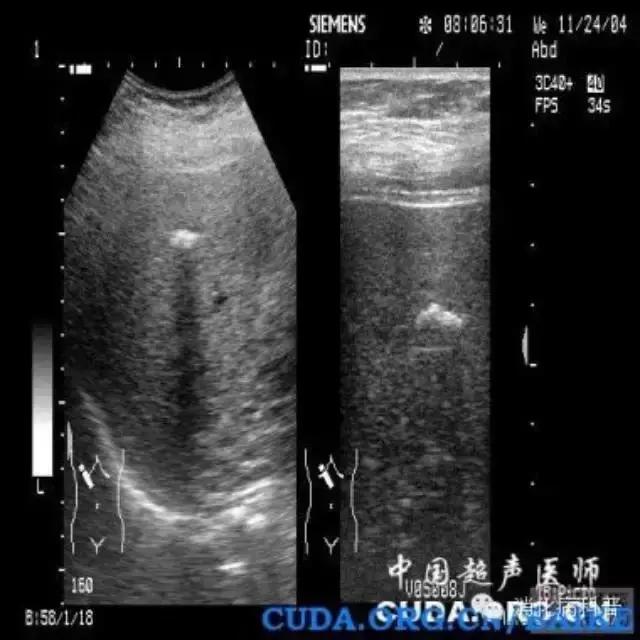

肝内钙化灶在B超上会出现类似结石一样的强回声,或CT检查时表现为肝内高密度影像。因此有时肝内钙化灶与肝内胆管结石容易相互混淆。所以很多人所谓的“肝内胆管结石”很可能只是肝内钙化灶。虽然肝内钙化灶和肝内胆管结石都有相似的强回声团及声影,但钙化灶一般不引起肝胆管扩张。

肝内胆管结石常见症状是肝区轻微疼痛,重者可引起剧痛,高热、黄疸等,并在胆管远端出现扩张。在超声检查时,肝内胆管且结石的“强回声光团”大都沿肝内胆管走向分布,这与钙化灶是完全不同的。所以B超发现肝内有“光团”后,要区别是肝内钙化灶还是肝内胆管结石,一个重要依据就是看远端胆管有没有扩张,而扩张的胆管内最容易形成淤滞性泥沙样结石。如果强光团周围出现液性暗区,同时伴有近侧胆管狭窄和远侧胆管扩张,更能确定为肝内胆管结石。

肝内钙化灶的B超图像特点是:呈“品字”或“等号”状分散的强回声,走行于胆管腔外,后方大多无声影或淡的声影,同时无肝内胆管扩张。